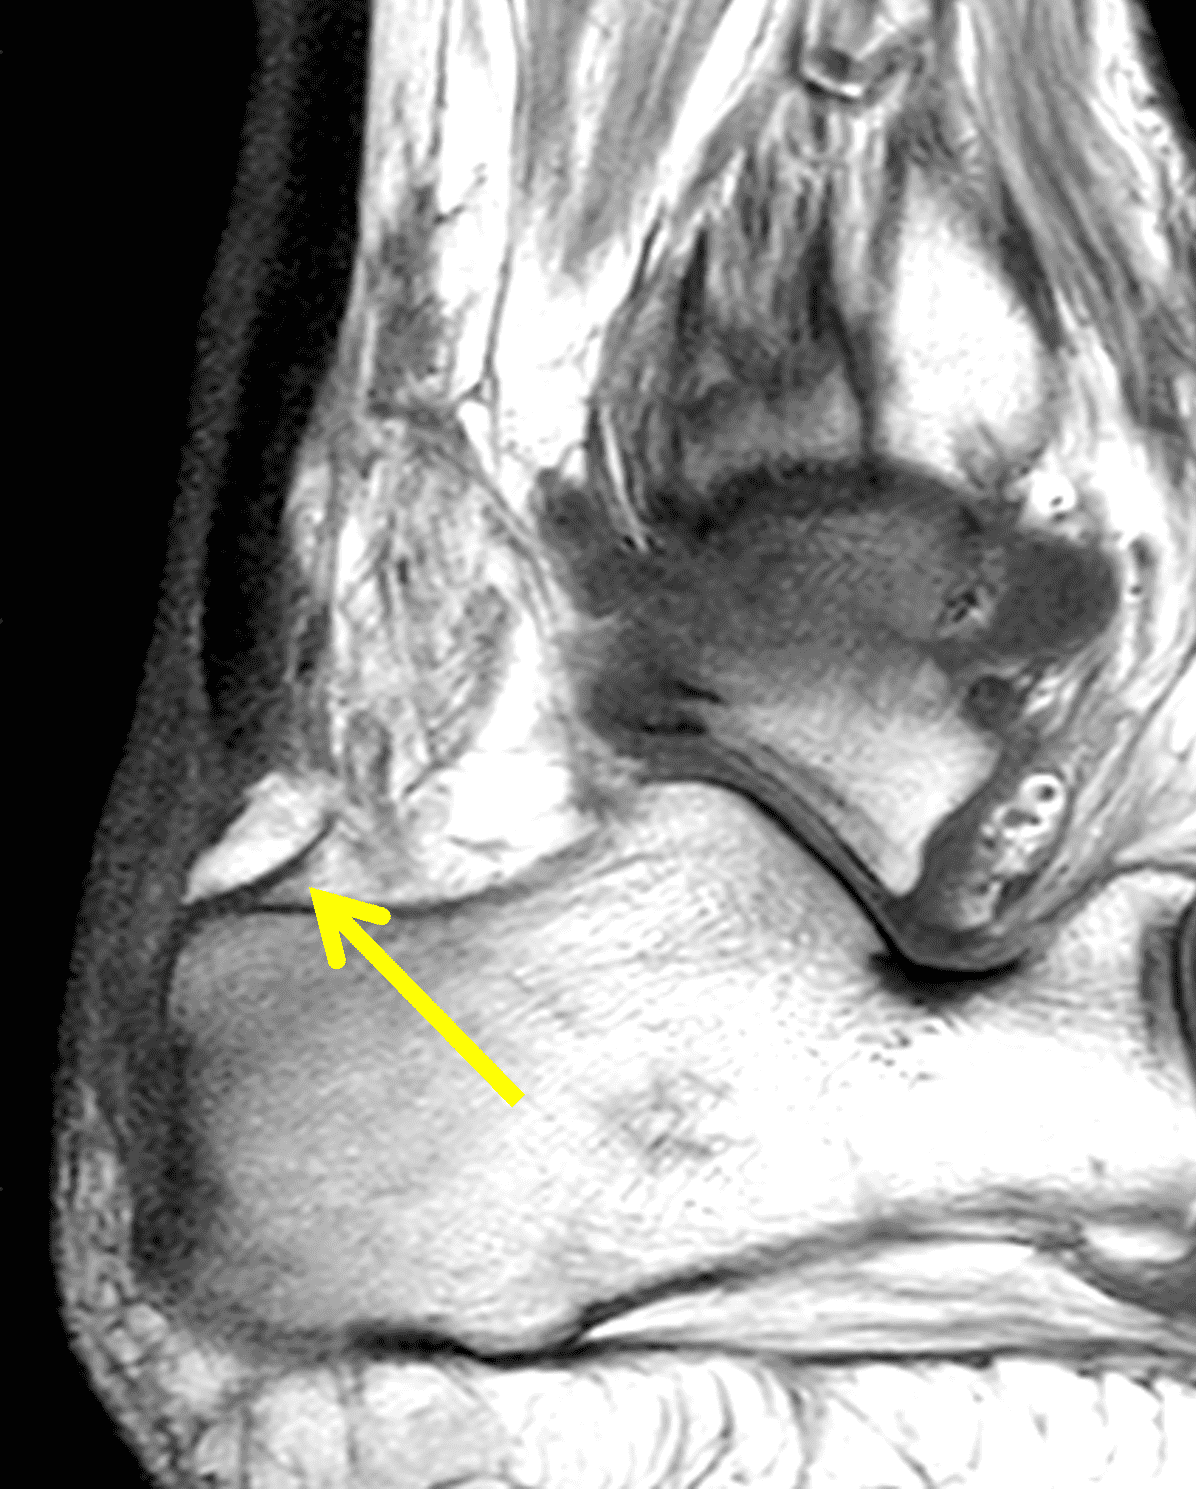

Figure 2: Complete Achilles tendon rupture. (2A) The lateral radiograph shows a thick and indistinct proximal Achilles tendon contour (arrows). (2B) A fat-suppressed T2-weighted image shows complete rupture of the tendon with a fluid-filled gap (yellow arrow) measuring 1.5 cm in length, located 10 cm cranial to the tendon insertion (blue arrow) and just distal to the edematous myotendinous junction (red arrow). The tear is superimposed on diffuse tendinosis. (2C) A sagittal T1-weighted image confirms the diffuse tendinosis. Fluid extends anteriorly into Kager’s fat pad (arrow) suggesting disruption of the anterior paratenon. (2D) A transverse fat-suppressed T2-weighted image through the proximal tendon shows no intact fibers (arrow), confirming the full-thickness rupture.